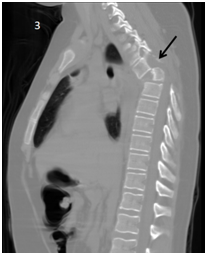

<strong>Figure 3 </strong> Thorax CT scan Sagital view showing T4 listhesis (black arrow).

Figure 3 Thorax CT scan Sagital view showing T4 listhesis (black arrow).

Two days after the in initial emergency room visit, the patient is admitted again with respiratory distress, fever and decreased oximetry by 88%. Because of the acute symptoms and clinical examination, pneumonia is suspected. IV antibiotic its initiated. Because previous the X-ray showed no other data, a computed tomography was performed, and pleural effusion was  confirmed with T4 listhesis (Figures 2-4).